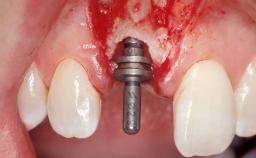

Immediate Flapless Placement of an Implant in a Maxillary Left Central Incisor Site

A 42-year-old female patient was referred to our clinic at the School of Dentistry of the University of São Paulo in November 2004, presenting a deficient restoration in the upper left central incisor. The clinical examination revealed no gingival retraction or any signs of gingival inflammation and, therefore, previous periodontal treatment was not considered. The patient presented a high lip line at full smile and a thin tissue biotype. This combination characterized a high-risk situation from an anatomic point of view, which required careful preoperative planning and cautious surgical execution.

Placement Protocol Immediate implant placement

Tooth Site Maxillary incisor or canine

Socket Morphology Single-root socket

Socket Integrity Sufficient, with intact bone walls

Bone Volume Sufficient, with intact walls